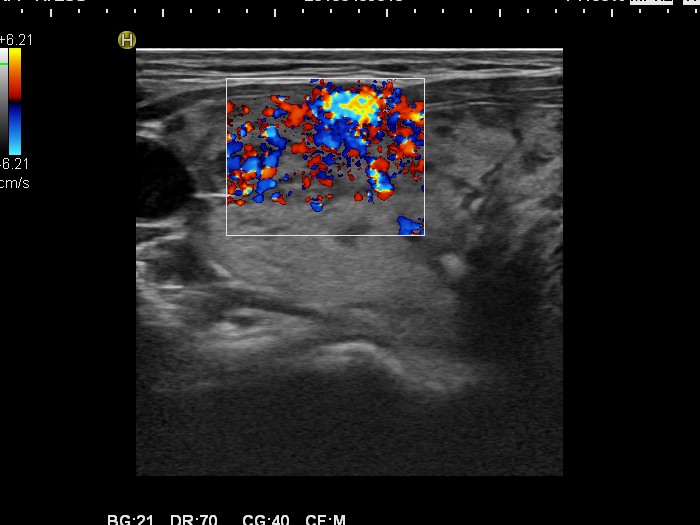

Graves' disease - Case 1049

Follow-up investigation 30 months after first visit (ultrasonographic picture 3)

Patient one year after discontinuation of thyrostatics in hyperthyroid state

Right lobe, transverse scan, Doppler mode. The vascularization is increased.